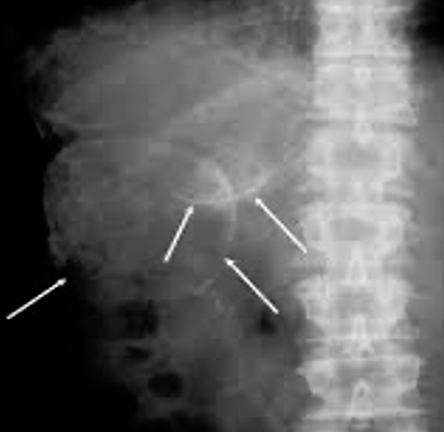

plain x-ray can show the calcification in the wall of the cyst

Calcification in the wall of the hydatid cyst in the right lobe of the liver